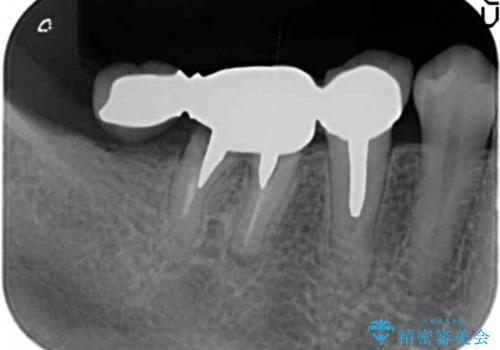

精査したところ、右下の奥歯(右下6)は割れており保存不可能な状態でした。

患者様のご希望により、右下大臼歯2本(右下76)のインプラント治療、右下小臼歯(右下5)の根管治療及び補綴治療を行いました。

割れていた歯の周囲組織の炎症が強く、骨の厚みが薄かったため、インプラント埋入時に骨増生(GBR)を行いました。

インプラントの種類:ストローマン BLT

クラウンの種類:ベレッツァクラウン(右下76)、ジルコニアクラウン スタンダード(右下5)